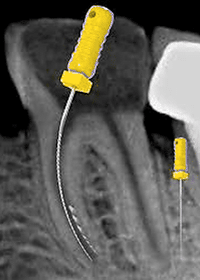

Step 3 — Pre-bend small file

Use #10 K-file with sharp bend at the last 2–3 mm.

A straight file will not find the pathway.

Step 4 — Watch-winding motion

Use gentle watch-winding movement beside the fragment.

Never apply pushing pressure.